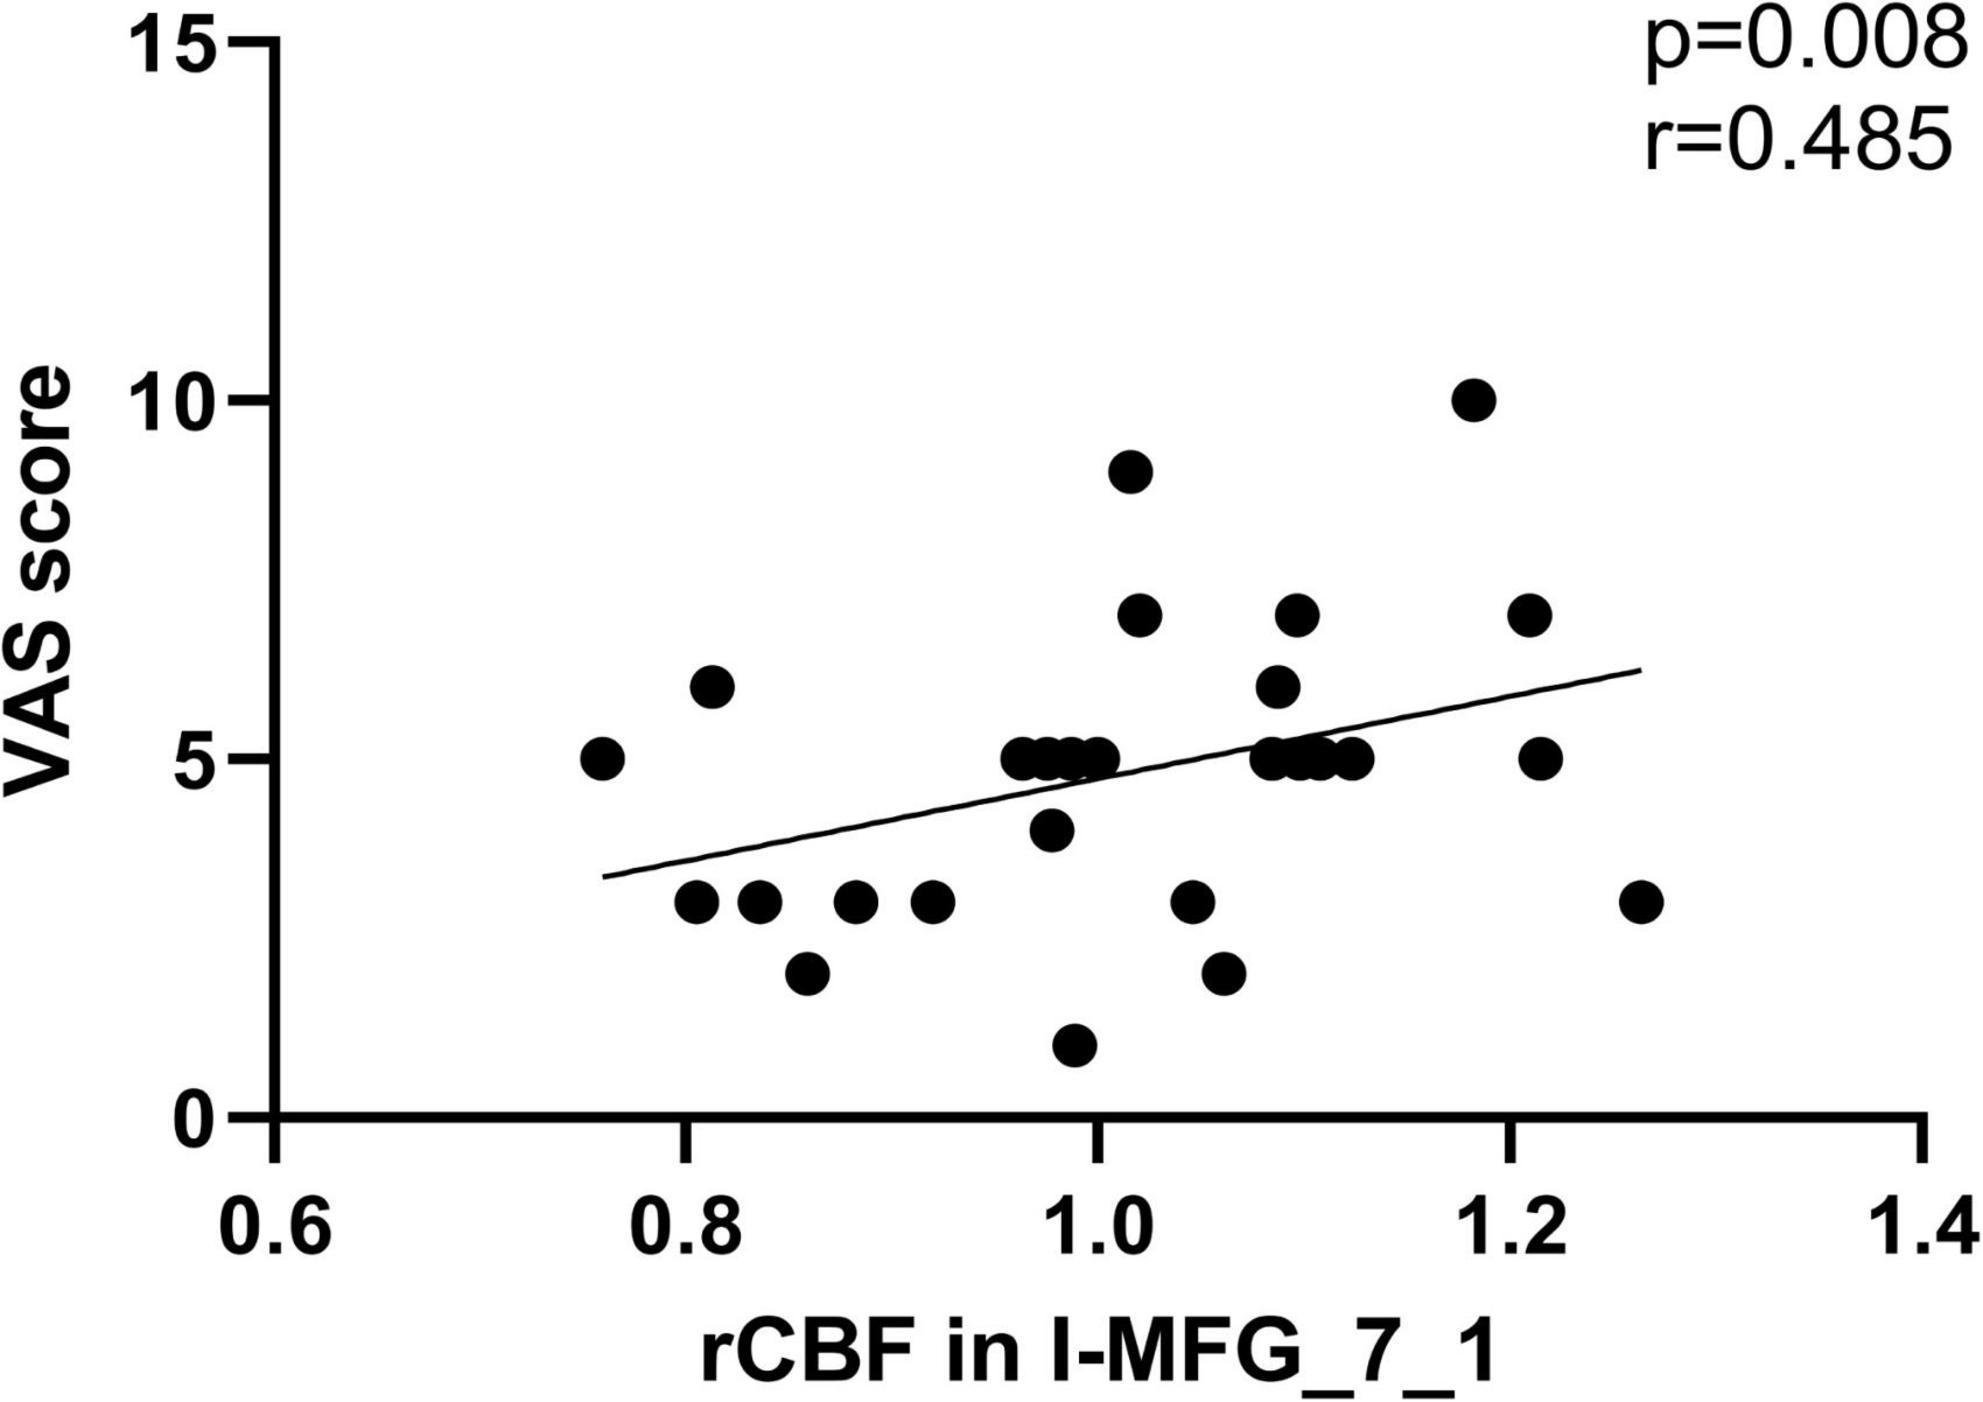

We found that the CBF in ipsilateral MFG_7_1 of SSNHL patients was positively correlated with VAS score (r = 0.485, p = 0.008) (Figure 7).

Figure 7. The significant correlations between the CBF changes and the clinical data in unilateral SSNHL patients. CBF in ipsilateral MFG_7_1 of SSNHL patients was positively correlated with VAS score (r = 0.485, p = 0.008).

Unilateral SSNHL patients exhibited decreased CBF in attention-related areas (bilateral dlPFC), primary motor cortex (PrG) and the associative somatosensory cortex (bilateral SPL). dlPFC involves in multi-sensory integration (Fuster, 2000), goal-driven attention (Jones and Graff-Radford, 2021), and as a core node in the executive control network (ECN) (Shen et al., 2020). Attention effects were reduced by the dlPFC lesions (Knight et al., 1981). A multimodal MRI Study indicated that the dlPFC plays an important role in the recruitment of the auditory area into cross-sensory processing in long-term bilateral SNHL patients (Luan et al., 2019). A voxel-based morphometry (VBM) analysis revealed gray matter changes in the SFG and MFG, suggesting a decreased use of ECN in chronic hearing loss patients (Husain et al., 2011). Several studies found the reduction of cortical thickness in SPL of children with SNHL (Shiohama et al., 2019; Qu et al., 2020), which is involved in processing motion stimuli (Qu et al., 2020) and cognitive control (Job et al., 2020). An age-related hearing loss ASL MRI study found the trend of reduced averaged perfusion involved multiple extra-auditory regions in the parietal and prefrontal cortex (Ponticorvo et al., 2019). Unilateral hearing loss causes the reduced attention of SSNHL patients in noisy environment by the deterioration of auditory processing, including speech perception and understanding (Ponticorvo et al., 2019). We speculate that reduced attention of SSNHL patients was related to CBF changes in the parietal and prefrontal lobes. In addition, we also explored the CBF differences of auditory-related cortex among the three groups (lSSNHL, rSSNHL, and HCs). We found that the increased CBF in left BA21 cadual and BA37 dorsolateral in patients with left-sided SSNHL, indicates that there might be a “superactivation” phenomenon in auditory-related areas (Xia et al., 2017). The same phenomenon was not found in patients with right-sided SSNHL, probably due to lateralization and the asymmetry in auditory processing (Tervaniemi and Hugdahl, 2003). The CBF in ipsilateral MFG_7_1 of SSNHL patients was positively correlated with VAS score tinnitus loudness. An fMRI study showed that the abnormal intensity of brain functional connectivity in patients with chronic tinnitus mainly occurred in the non-auditory brain region, especially in the prefrontal cortex (Araneda et al., 2018). Tinnitus may be produced to reduce perceptual uncertainty caused by peripheral auditory deafferentation (Morcom and Friston, 2012), which can explain the reason most SSNHL patients in this study accompanied by tinnitus.